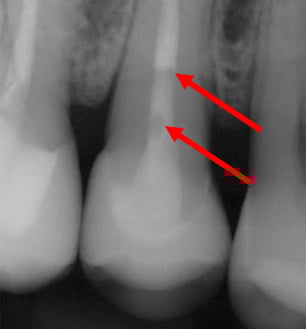

1. Auf Röntgenbildern sichtbare Blasen

Auf der Röntgenaufnahme dieses endodontisch behandelten Zahnes sind zwei Blasen zu sehen. Das ist peinlich und den Patienten schwer zu erklären. Diese Blasen machen Endodontologen verrückt.